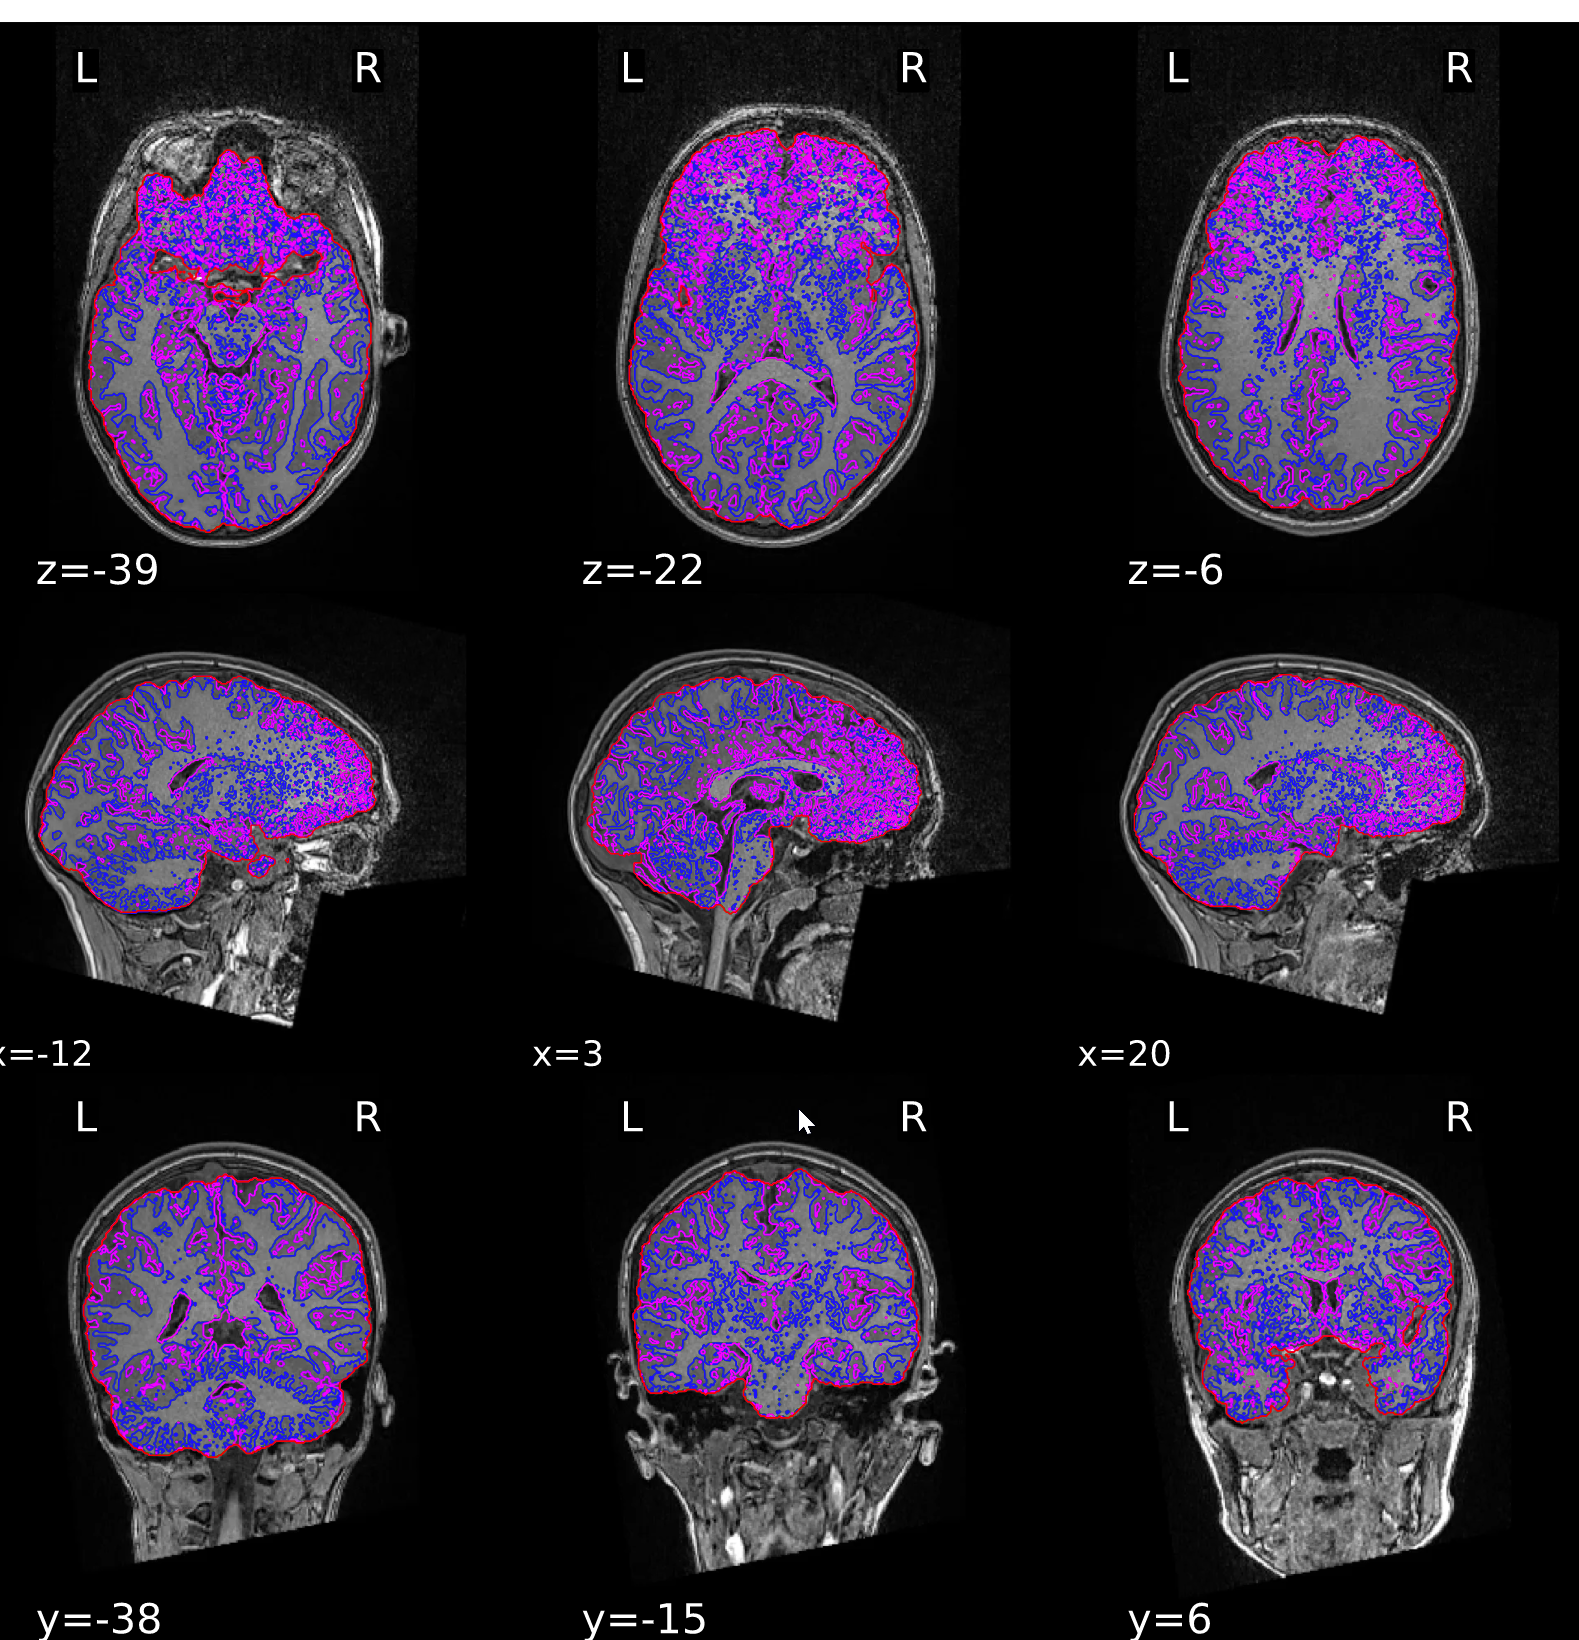

ds000200/reportlets/fmriprep/sub-2014/anat/sub-2014_T1w_seg_brainmask.svg